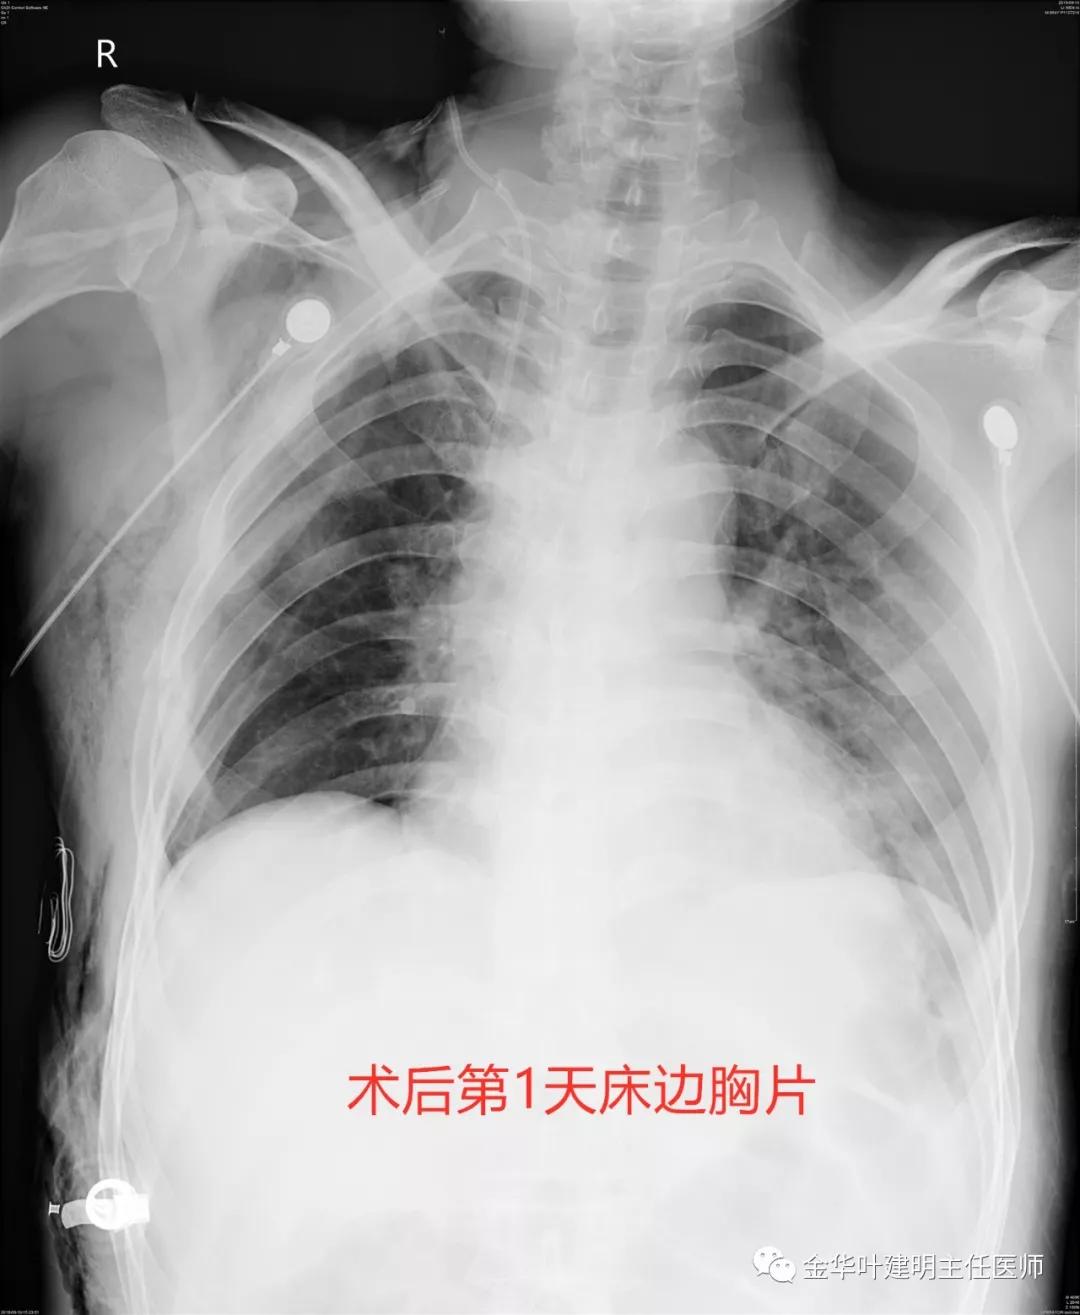

很快,经过术前准备,我们为其安排手术,手术时游离下肺韧带、清扫纵隔淋巴结、离断奇静脉、解剖肺静脉、下叶肺动脉与中叶肺动脉、适当游离上叶支气管,各项看操作有条不紊,最后于上叶支气管开口处切断,右主支气管处切断,移去标本,再用3-0无损伤线进行右上叶支气管与右主支气管的吻合,手术非常顺利。术中快速切片示病理为鳞癌,切缘阴性。术后膨肺时吻合上去的右上叶轻松可膨胀开,说明无狭窄情况;注生理盐水入胸腔并膨肺发现吻合口没有任何哪怕一点点漏气,说明吻合满意牢靠。下面是手术次日的胸片:

可见右上叶膨胀非常好!